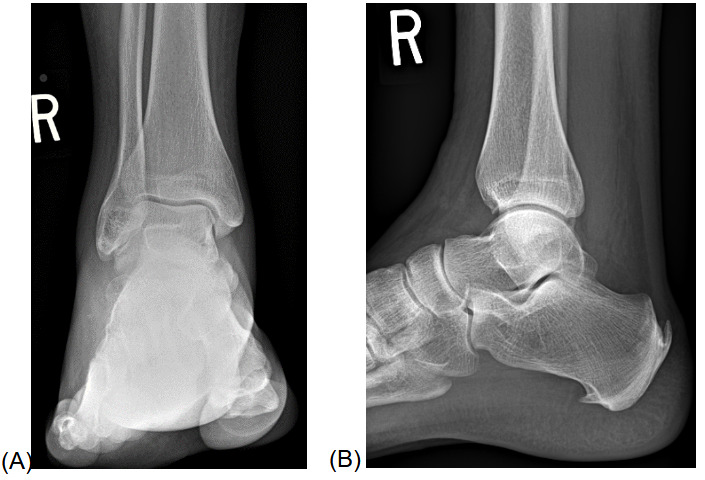

An AP, lateral, and oblique image was performed on the right ankle 2 days after the injury (Figure 1A, 1B). No fracture was evident; however, there was prominent soft tissue swelling, most prominent overlying the lateral malleolus, with evidence of mortise-joint effusion. One week later, a repeat radiographic examination was performed to exclude an occult fracture. The patient’s pain persisted, and 1 week later, images were repeated (Figure 2A, 2B). New radiographs demonstrated mildly reduced swelling of the ankle and mild mortise-joint effusion. MRI was recommended to help assess for possible internal joint derangement.

_and_lateral_(b)_ankle_radiographs_3_days_after_injury.png)